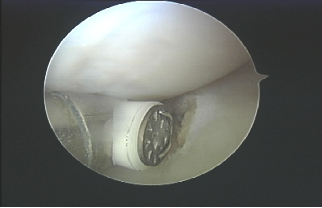

04 Product Detail Picture

Angle 90°, sheet electrodes, shaft length 135mm, outer diameter 4.0mm, suitable for large-area soft tissue cutting and ablation. It has a suction function and can accurately and quickly remove various tissues and effectively absorb soft tissue debris and air bubbles at the same time to ensure a clear surgical field.

05 Application display